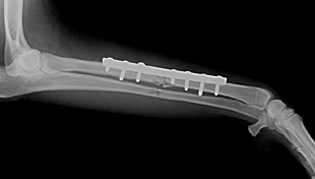

Todos los procesos ortopédicos y traumáticos suponen un stress y un mayor o menor grado de dolor e inhabilitación que disminuye la calidad de vida de nuestras mascotas.

En nuestro servicio de traumatología intentamos buscar la solución a los problemas ortopédicos que afectan a sus mascotas de una forma individualizada, adaptándonos a las características de cada paciente: especie, raza, edad, carácter y estilo de vida.